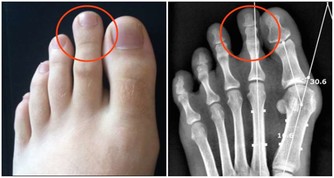

晚期症狀:

而當癌細胞進一步擴散,病情逐漸惡化時,會影響到消化系統以外的部分。

例如患者的糞便會參有血跡,體重也異常減輕,時常感到疲倦乏力,由於胃部有積液還會引起胃脹胃痛;

嚴重時還會導致貧血和呼吸困難,皮膚和眼白也會開始泛黃。